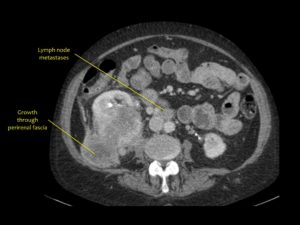

МРТ – один из методов диагностики солидного рака

- лучевая диагностика, включающая в себя ультразвук, рентген, МРТ, чаще применяется для экзофитных новообразований, позволяет определить границы распространения опухолей их плотность и структуру;